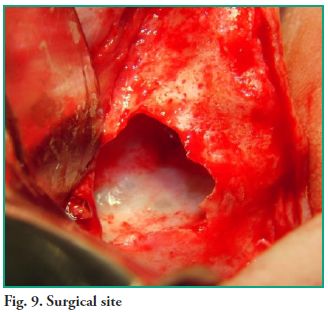

An ostectomy was performed using a rotary instrument and copious irrigation with normal saline is applied to enlarge the fenestration in order to improve visibility. The lesion was fully removed with sinus lift curettes using the enucleation and curettage technique, and the exeresis of the bone septum that divided the lesion was performed afterwards (Figs. 7, 8 and 9). Finally, closure was performed using continuous suture with 5-0 nylon thread (Fig. 10).

An ostectomy was performed using a rotary instrument and copious irrigation with normal saline is applied to enlarge the fenestration in order to improve visibility. The lesion was fully removed with sinus lift curettes using the enucleation and curettage technique, and the exeresis of the bone septum that divided the lesion was performed afterwards (Figs. 7, 8 and 9). Finally, closure was performed using continuous suture with 5-0 nylon thread (Fig. 10).